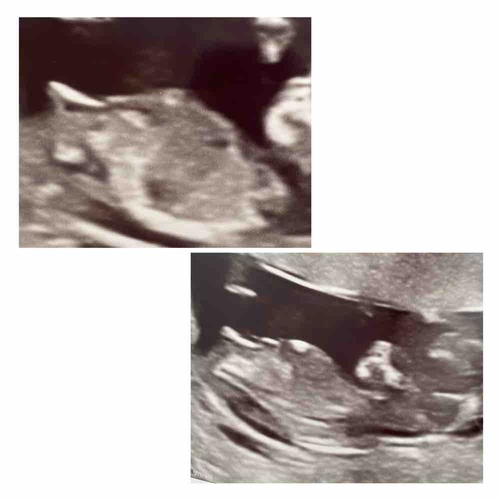

Iemand een idee? 💙💗 Denk dat de nub vrijwel niet zichtbaar is? De kleine bewoog flink tijdens de echo. De links bovenste is van de 12+2 de andere 3 van vandaag 14+2 met de 13 weken echo. Over 2 weken met 16+4 hebben we de geslachtsbepaling.

Hier nog een andere foto van de echo

Op advies zet ik m hier ook nog even in🤭🤗 wie kan het al zien? Echo is van de 13 weken echo vandaag 13+2. Denk zelf meisje te zien

Is hij zo misschien wat duidelijker? Dit is eerlijk de enigste foto die ik mee heb waar ik de nub zie😅